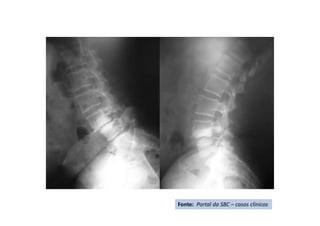

• Cifose pós-traumática

• Resumo do caso: Queda da própria altura com diminuição de força de

membros inferiores de forma gradativa.

• Paciente (dados): Sexo feminino, 54 anos

• História: Queda da própria altura durante internação hospitalar em outro

serviço para tratamento de crise de ativação do LES há 6 meses. Apresentou

diminuição de força de membros inferiores de forma gradativa. Foi avaliada

no serviço de origem e realizado TC e aventada a hipótese de mielite

transversa. Foi encaminhada ao CRER para reabilitação. Nesse momento

apresentava apenas parestesia em MMII e FM grau 0 (ASIA B).

• Diagnóstico(s): Consolidação viciosa de T5, com cifose pós-traumática e

compressão medular (ASIA B)

• Antecedentes de Lúpus (LES), uso crônico de corticóide e tabagismo severo

• Tratamento(s): Realizada vertebrectomia com descompressão medular e

reconstrução com Mesh CAGE e artrodese de T2 a T8 por via posterior.

• Seguimento ("Follow up"): PO 1 ano com boa melhora funcional da

paciente.

• Resultado Final: Paciente apresentou melhora gradativa da força muscular e

da função, estando hoje com força muscular grau IV em MMII, conseguindo

deambular e inclusive subir e descer escadas com apoio (ASIA D).

Fonte: Portal da SBC – casos clínicos

RX da coluna torácica -

Perfil